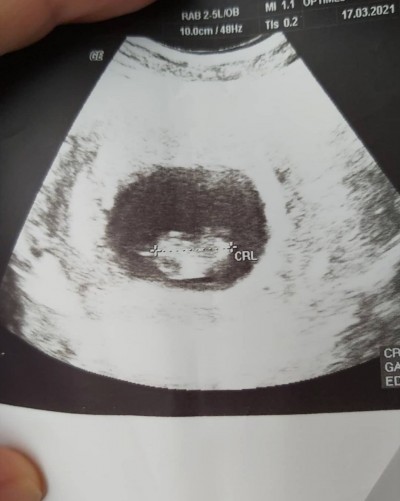

Cinsiyet tahmini yapabilirmisiniz kizlar

Gebelik haftası

10

10 haftalık bebeğe hele de şu görüntüye nasıl tahmin söylensin

Kese yuvarlak normalde kız bebeklerde kese yuvarlak olur benimde 2 kizim var onlara da benzetim hakinda hayırlısı canm